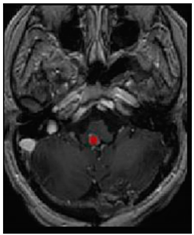

Three cases from the NTUH dataset showing representative results of different models were shown in Table 2, Table 3 and Table 4. The overall dice scores of these networks on the NTUH dataset ranged from 0.33 (DeepMedic) to 0.51 (V-Net). Table 5 shows the detailed performance of each network tested with the NTUH dataset.

Table 3. Predictions with average dice scores.

Ground truthDeconvNetDeepMedic

Applsci 11 09180 i007 Applsci 11 09180 i008 Applsci 11 09180 i009

PSPNetU-NetV-Net

Applsci 11 09180 i010 Applsci 11 09180 i011 Applsci 11 09180 i012